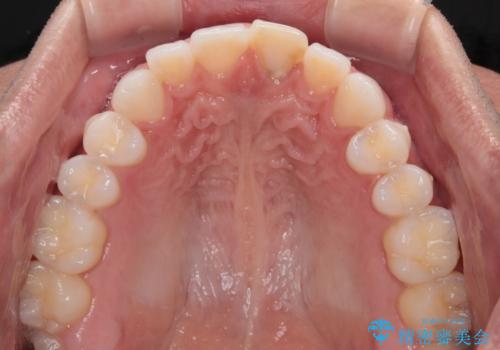

- 以前ぶつけて神経を取り除いてから、徐々に変色してきた前歯が気になるとのことで来院された患者様です。

神経を取り除いた歯の変色はホワイトニングでは十分に改善できないため、オールセラミッククラウンにて補綴治療を行うこととしました。

定期的にホワイトニングをされていることや、前歯の歯列が左右非対称であることから、色合いや形態の修正が多くなることが予想されたため、オーダーメイドタイプのグレードを選択していただき、治療を進めて行くこととしました。